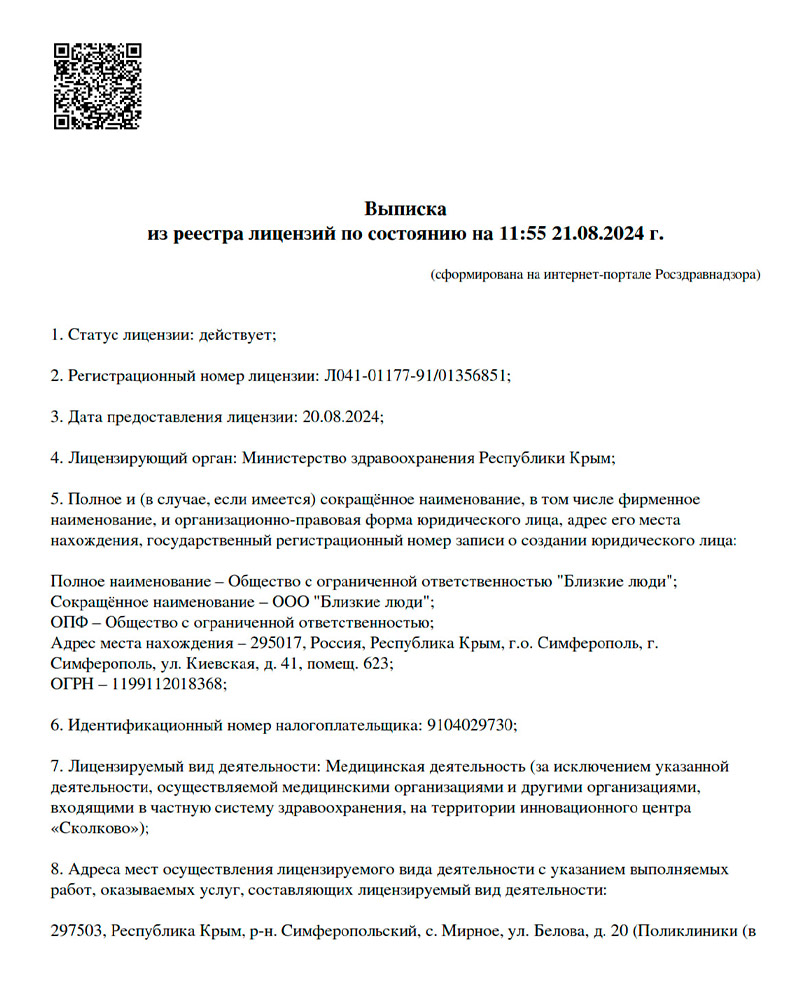

Официально

Лицензия на медицинскую

деятельность